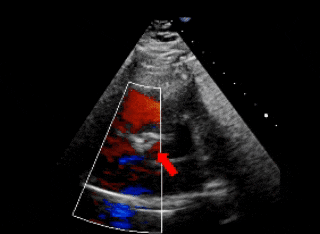

超声下可见右冠窦与右心房相通,主动脉短轴切面示类似膜周部室缺

保留导丝技术,展开封堵器左盘(左);超声下可见左盘面贴靠主动脉侧(右)

右盘面展开后,前推钢缆使其成型(左);超声下可见双盘面骑跨(右)